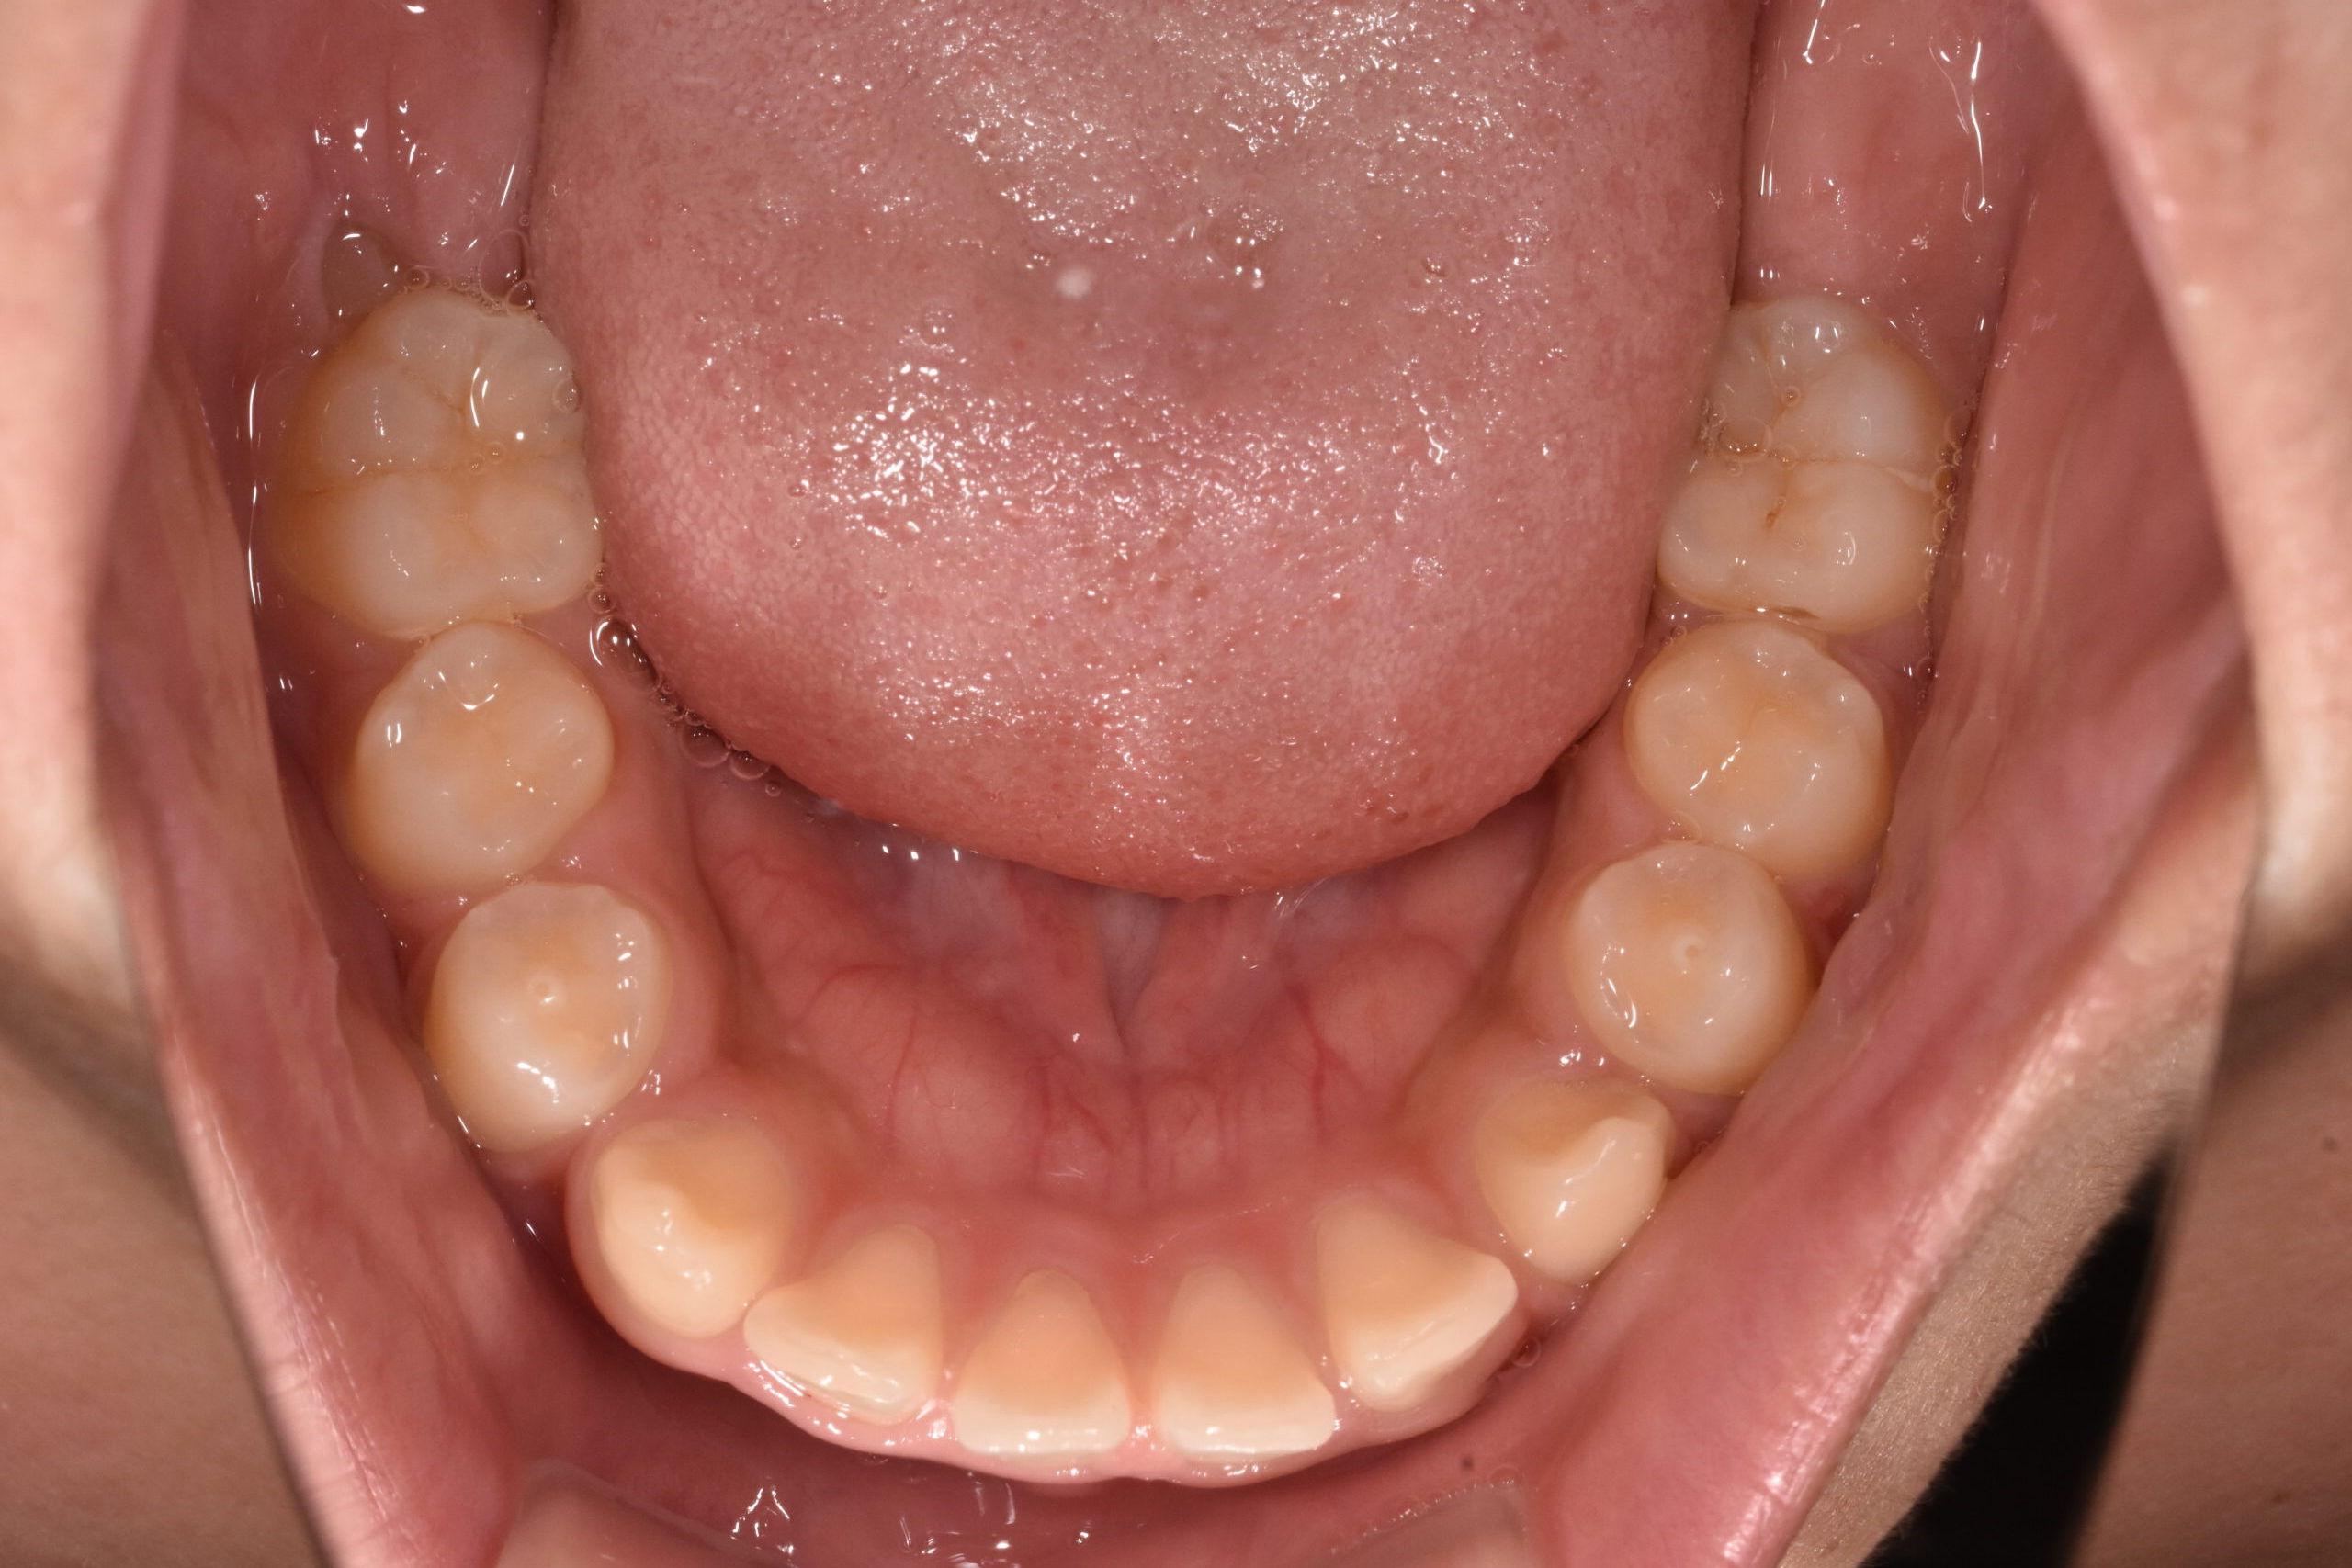

上下顎前突 10歳8ヶ月 男の子

10歳8ヶ月 男子

治療前

骨格:上下あごともに前方に出やすい傾向(上下顎前突)

歯並び:前歯の前方への突出(出っ歯傾向)

成長を利用した1期治療にて、マウスピース型装置や矯正装置を用い、歯並びと口元のバランスの改善を行いました